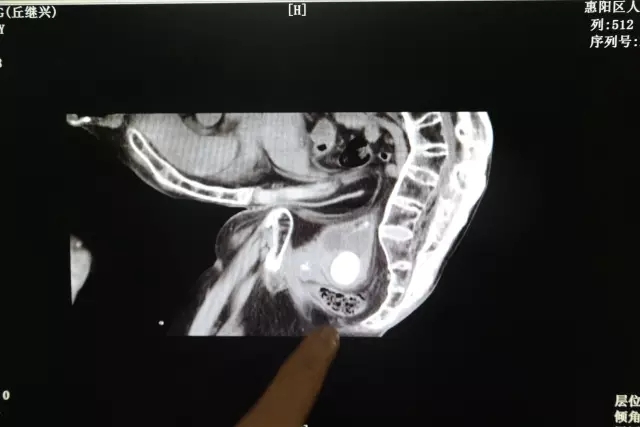

我院泌尿外科接診後(hòu)經(jīng)檢查發(fā)現,老伯的膀胱結石已經(jīng)達到直徑4cm,嚴重堵塞尿道(dào)口,緻使他排尿困難,尿路感染嚴重。泌尿外科團隊經(jīng)過(guò)慎重的考慮,認爲手術治療可采用超聲腔内碎石系統,進(jìn)行微創碎石。我院在9月引進(jìn)微創新技術已經(jīng)成(chéng)功治愈幾十名相似病例的患者,技術成(chéng)熟,雖然老人的病例特殊,手術難度大,但我院泌尿外科團隊有能(néng)力有信心爲老伯解決痛苦。

據鍾主任介紹說(shuō),老伯患有嚴重的強直性脊柱炎,腰呈90度彎曲,盆腔與大腿貼到一塊,沒(méi)辦法伸直,按照正常的體位經(jīng)腹取石不可行,隻能(néng)經(jīng)尿道(dào)取石,而且老伯年紀大了,麻醉也是個大難題,經(jīng)過(guò)泌尿外科、麻醉科的專家們多次會(huì)診後(hòu),制定了治療方案。

12月3日,醫院給丘老伯實施了手術,對(duì)老伯進(jìn)行全麻,以端坐的體位,手術使用醫院新引進(jìn)的超聲腔内碎石系統,導管經(jīng)尿道(dào)進(jìn)行碎石,經(jīng)過(guò)一個多小時(shí)的手術後(hòu),老伯體内直徑4cm的結石成(chéng)功擊碎取出體外。第二天早上,老伯有胃口了,喝了一碗粥,第三天就(jiù)吃了滿滿一碗飯。